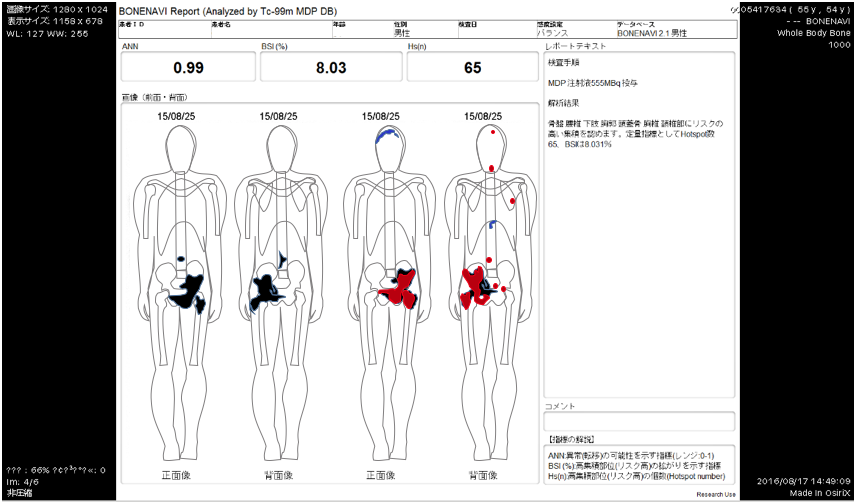

前立腺 癌 骨シンチ. 外部サイトへ whats 前立腺がんを離れます リンク先の第三者のサイトについてのお問い合わせはそれぞれのお問い合わせ先にご連絡くださいwhats前立腺がんはその第三者のサイトの内容等についての責任は負いかねますのでご了承ください. 平成17年3月の人間ドックで前立腺癌が疑われ当時49歳その年の8月に前立腺癌が発見され 9月28日に前立腺癌の手術を受けました当時50歳 前立腺癌はpsa 検査をすることにより確実に早期発見のできる癌ですがその年に私がpsa 検査を受けたのはたまたまその年の検査項目にpsa. 骨シンチで転移したところが真っ黒になっているのを見たときは痛かったが今はホルモン療法でpsaも下がり痛くないので放射線治療は受けないことにした前立腺がんの語り 認定npo法人 健康と病いの語り ディペックス.

全身骨シンチグラフィ 乳癌 肺癌 前立腺癌等の骨転移病巣の検出

前立腺がんの検査 骨シンチグラフィー 前立腺がんの治療と名医

主な核医学検査 骨 骨シンチグラフィ 核医学検査のご案内 医療関係者

骨シンチグラフィーとは 佐賀大学病院放射線科アンオフィシャル

第15回日本核医学会春季大会ランチョンセミナー 骨転移の診断 治療

全身骨シンチグラフィ 乳癌 肺癌 前立腺癌等の骨転移病巣の検出

骨シンチグラフィによる骨転移の診断 Bone Scan Ct Mri画像診断